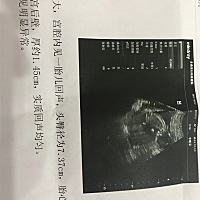

帮忙看男宝还是女宝?